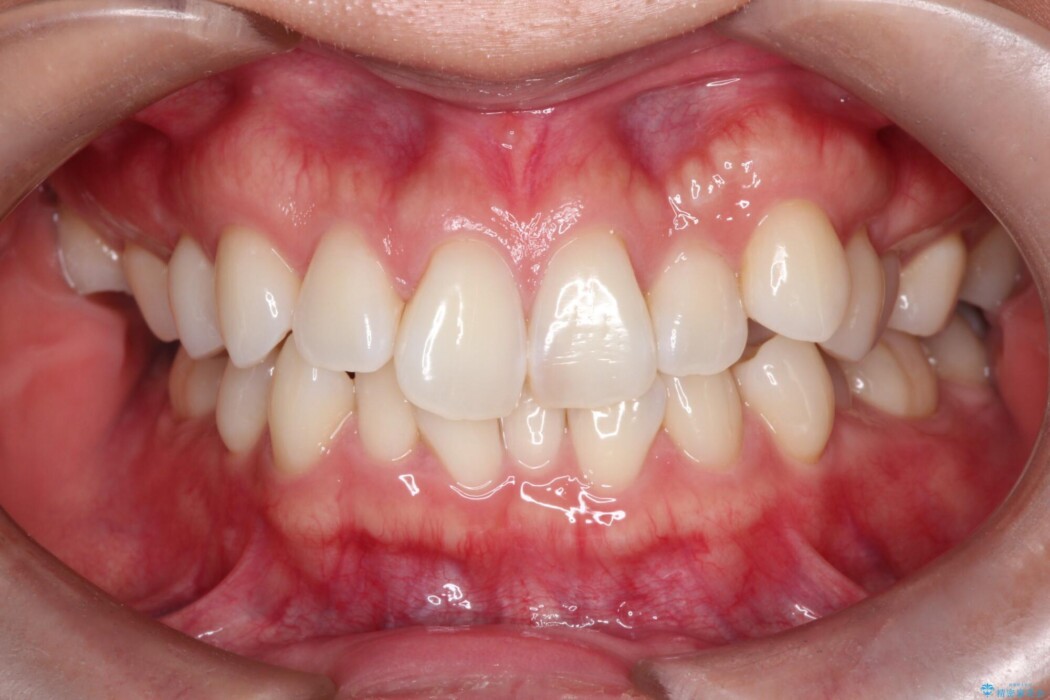

トランスパラタルアーチを用いて右上7番目の歯を内側へ誘導し、正しい位置へと修正しました。

まずはこの装置で奥歯の土台を安定させつつ、ワイヤー装置による繊細な歯の移動を組み合わせることで、非抜歯で歯列全体のアーチを整えていきました。シザーズバイトが解消されたことで、奥歯でしっかりと物を噛めるようになり、顎の動きもスムーズに改善されました。

治療完了後、前歯のガタつきはきれいに整い、上下の奥歯も理想的な位置で噛み合うようになりました。非抜歯での治療により、ご自身の歯をすべて残したまま、機能的で美しい歯並びを実現することができました。